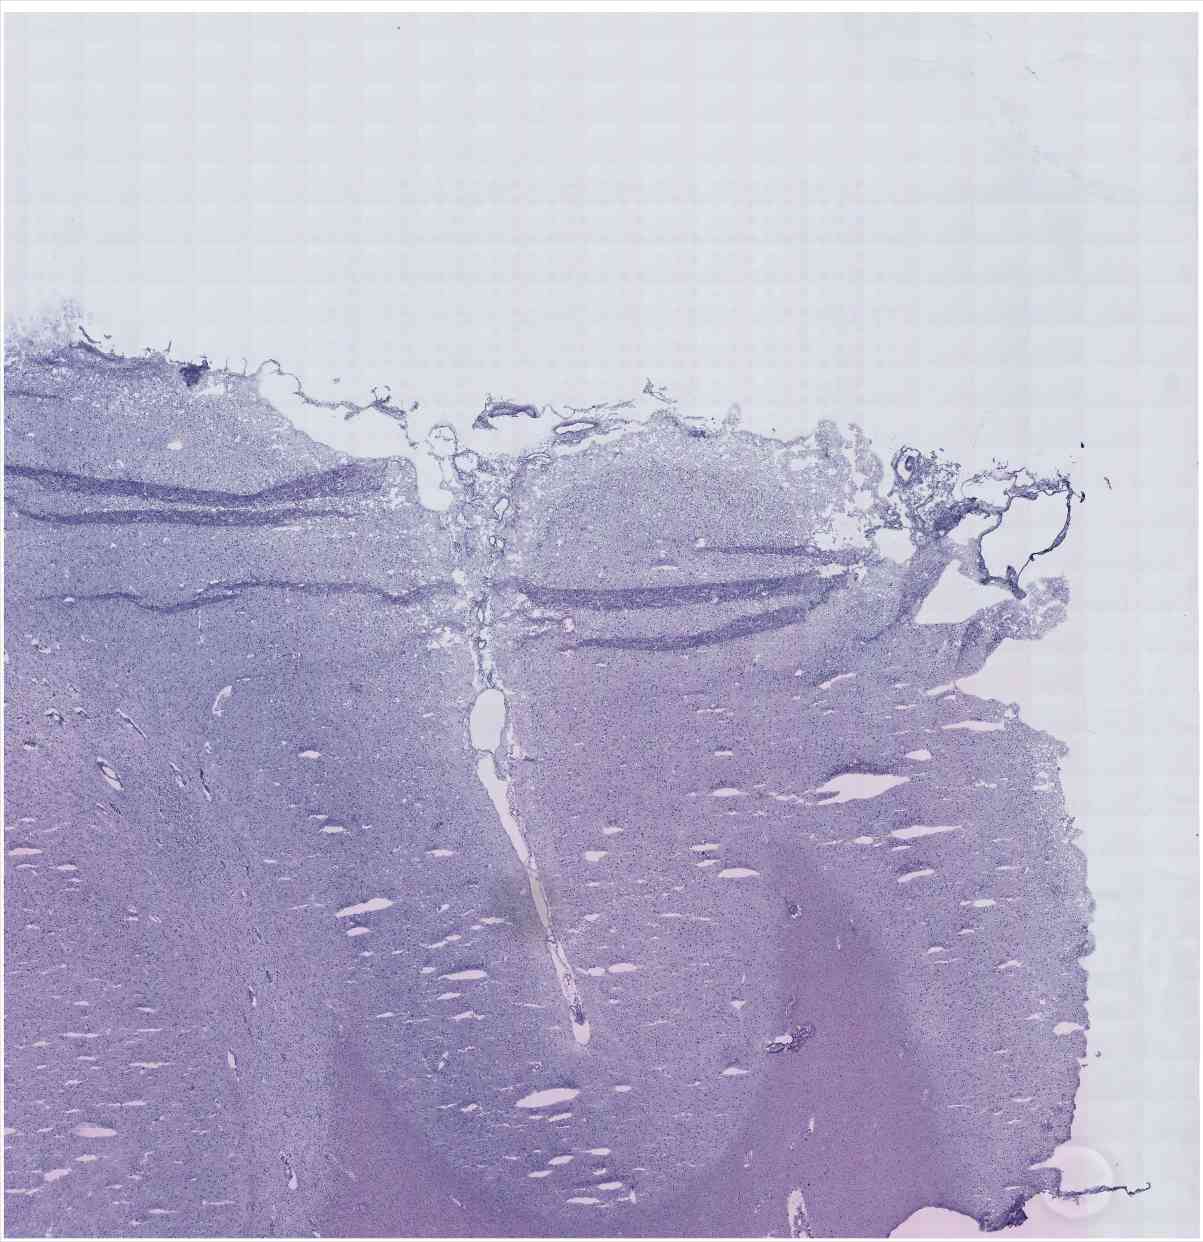

Chip 067 Well C2